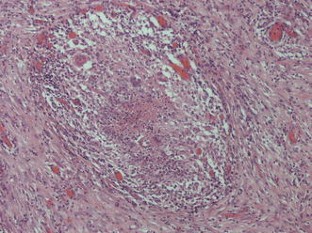

The histopathological mimics of inflammatory bowel disease: a critical appraisal

The pathological diagnosis of inflammatory bowel disease (IBD) is often difficult because biopsy material may not contain pathognomonic features, making distinction between Crohn’s disease, ulcerative colitis and other forms of colitides a truly challenging exercise. The problem is further complicated as several diseases frequently mimic the histological changes seen in IBD. Successful diagnosis is reliant on careful clinicopathological correlation and recognising potential pitfalls. This is best achieved in a multidisciplinary team setting when the full clinical history, endoscopic findings, radiology and relevant serology and microbiology are available. In this review, we present an up-to-date evaluation of the histopathological mimics of IBD.

Fig. 1